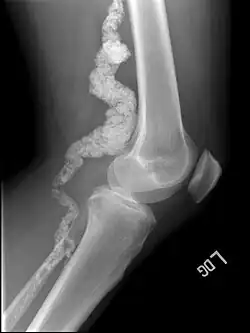

| A knee x-ray of a person with ACDC | |

Arterial calcification due to deficiency of CD73 (ACDC) is a rare genetic disorder that causes calcium buildup in the arteries and joints of the hands and feet, and other areas below the waist.[1] Although patients exhibiting these symptoms have been identified as early as 1914, this disorder had not been studied extensively until recently. The identification of the specific ACDC gene and mutations occurred in 2011. ACDC is caused by a mutation in the NT5E gene, which prevents calcium-removing agents from functioning.[1][2] Patients with this mutation experience chronic pain, difficulty moving, and an increased risk of cardiovascular problems.[1][2] In experiments at the molecular level, treatment with adenosine or a phosphatase inhibitor reversed and prevented calcification, suggesting they could be used as possible treatment methods.[1] There is currently no cure for ACDC, and patients have limited treatment options, which focus primarily on the removal of blood calcium and improving mobility.[1][2]